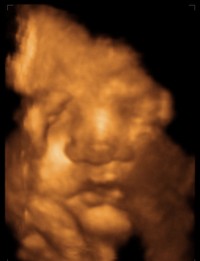

Bocsánat a zavarásért, egyszer már írtam Nektek, illetve tettem fel 4D-s képeket az akkor 13 hetes pocaklakó Kisfiamról, hogy lássátok, milyen csoda ez az egész... 7 centis, és mindenük megvan.